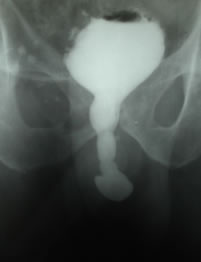

Микционная цистоуретрография – контраст

заполняет простатическую перепончатую проксимальную

часть бульбозной уретры. |